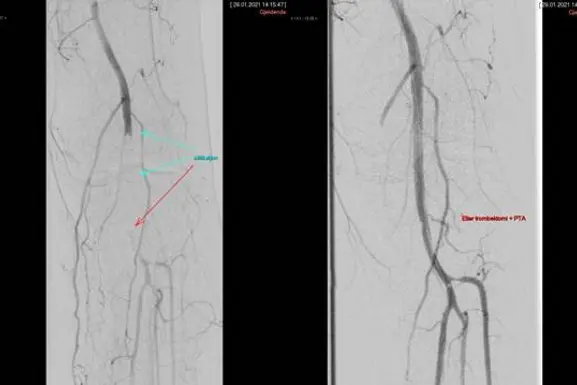

FØR OG ETTER. Bildet viser tett blodåre i knehasen før støvsuging (til venstre) og

åpen blodåre etter. (Pasienten har samtykket til bruk av bildene)